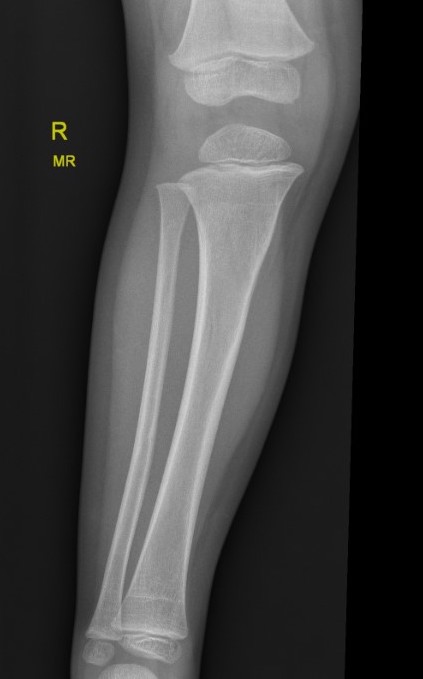

Manipulation and casting of malaligned Cozen fracture under anesthesia